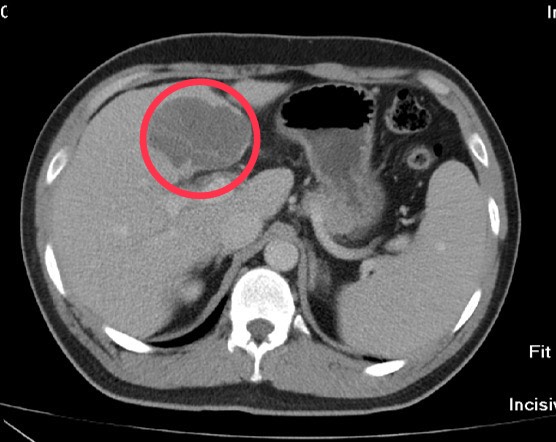

圖:經化療、免疫療法及釔 - 90 放射栓塞術的三管齊下策略,肝腫瘤順利縮小,順利手術/臺中榮總提供

33 歲吳先生去年因解黑便及吐血就醫,確診胃癌並肝轉移,肝腫瘤達 11.8 公分、佔據 1/3 肝臟,傳統化學治療效果有限,臺中榮總團隊首次運用化療加免疫療法,結合釔 - 90 放射栓塞術的三管齊下策略,成功縮小胃及肝腫瘤 (肝腫瘤縮小至 6.2 公分),使其順利接受手術切除,術後恢復良好。此策略突破晚期胃癌治療瓶頸,為患者帶來新希望。

近年免疫療法問世,通過激活免疫系統攻擊癌細胞,研究證實對治療胃癌有效,晚期胃癌一線免疫治療已納入健保給付,臨床多採化療加免疫療法雙管齊下治療。釔 - 90 內放射治療(Y-90 SIRT)透過放射性微球體,將高劑量放射線精確投遞至肝腫瘤,殺死癌細胞,有效縮小腫瘤,且增加病人可接受手術治療的機率,將原本柔軟如豆腐的肝腫瘤變硬,減少術中腫瘤破裂的風險,是近年治療肝腫瘤新方法。

臺中榮總一般外科、影像醫學部介入性診療放射科和腫瘤內科團隊結合化療、免疫治療及釔 - 90 放射栓塞術三管齊下,以化學藥物殺死癌細胞,搭配免疫療法增強腫瘤微環境免疫反應,再用釔 - 90 微粒攻擊肝內腫瘤,有效縮小病人胃和肝腫瘤,以利完整切除腫瘤手術。